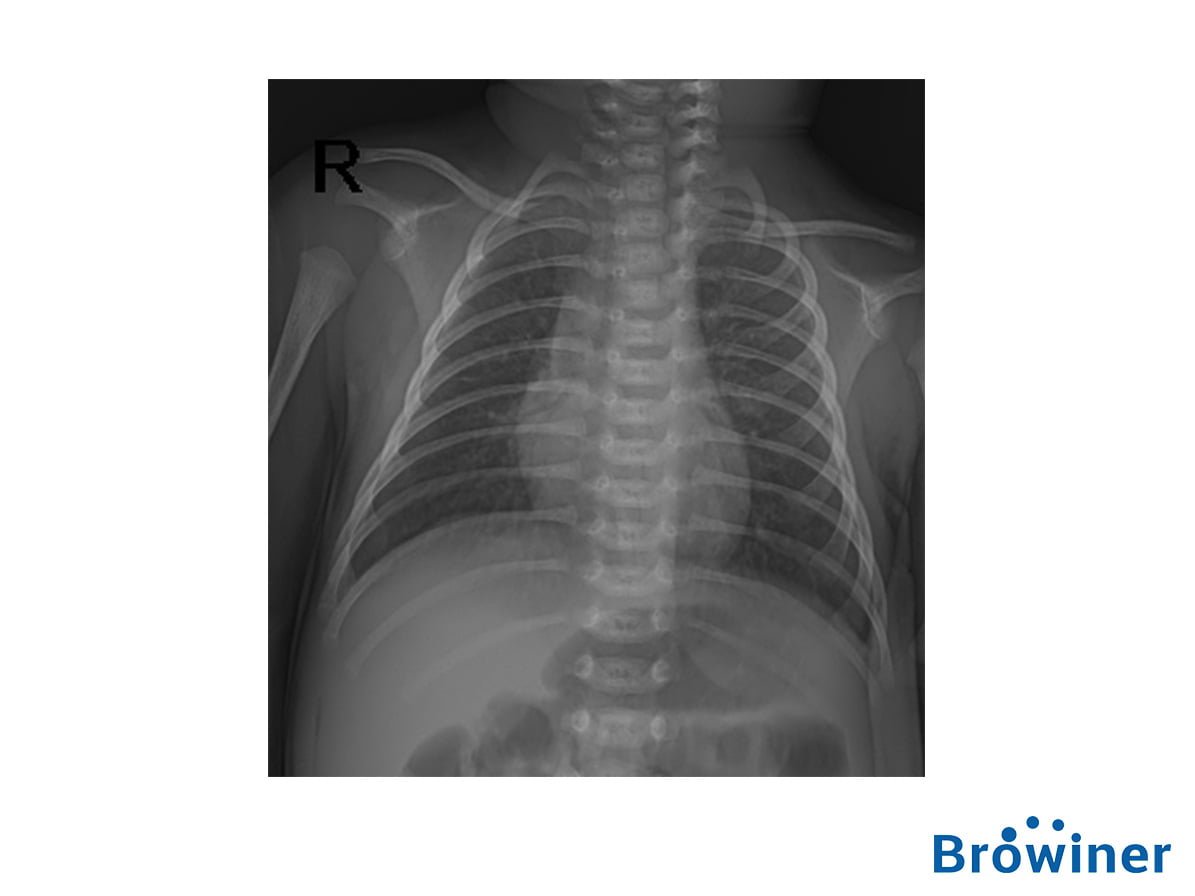

El Emer/Neo DR es un equipo de rayos X altamente integrado que ahorra tiempo a los doctores y enfermeras en situaciones de emergencias.

Con un cuerpo delgado y un diseño compacto, Emer/Neo DR se puede transportar y usar fácilmente en un lugar complicado y estrecho.

Con una baja dosis de radiación y la compatibilidad con la incubadora como sus principales características, Emer/Neo DR se puede usar dentro de la incubadora infantil, lo que brinda una mayor atención integral para los bebés.